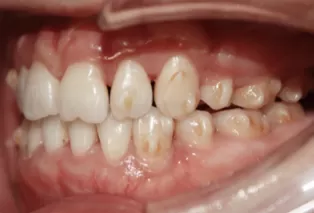

Intraoral photos